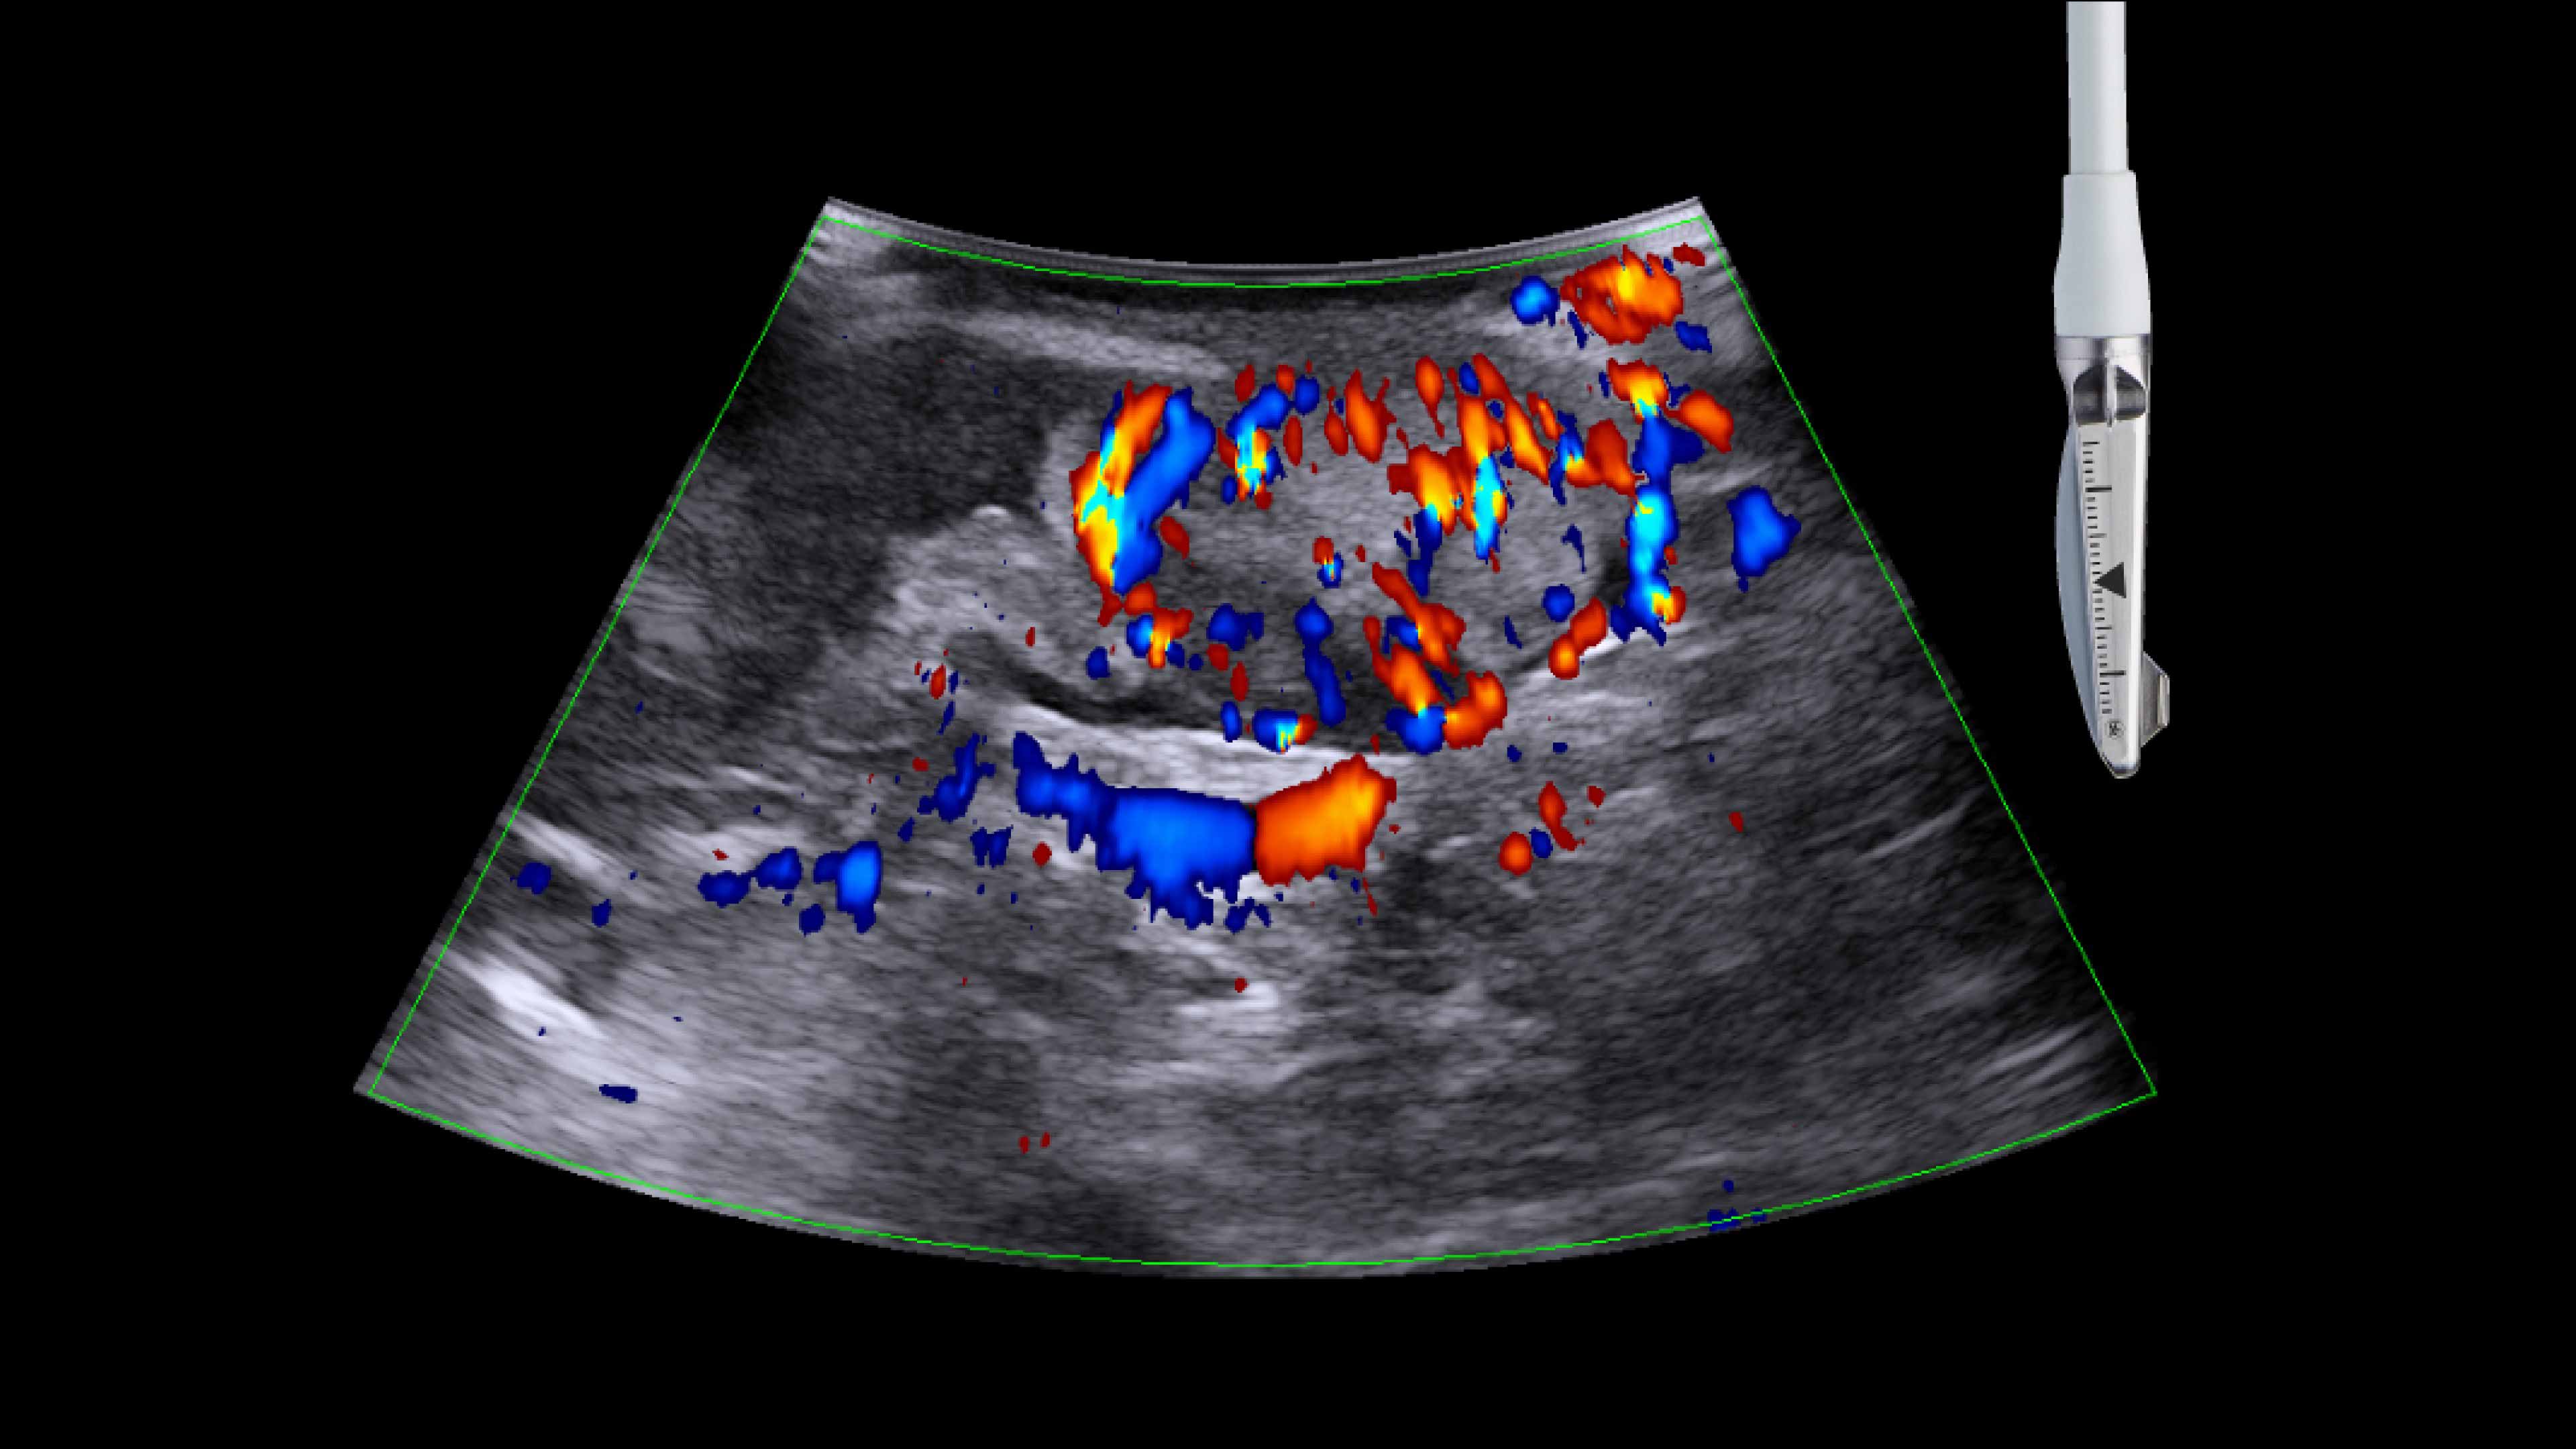

Active imaging supports liver and pancreas tumor resection procedures by helping you visualize complex anatomical variations and relationships to vascular structures, identify tumor location, define adequate margins of resection, and assess surgical planning.

Active imaging with intraoperative ultrasound supports critical decision-making in open or minimally invasive tumor resections.

• Visualize complex anatomical variations.

• Identify tumor location, proximity, and invasion of vasculature.

• Define adequate margins of resection.

• Understand relationship to vascular structures.

• Assess surgical planning and check for vessel patency at the end of the procedure.